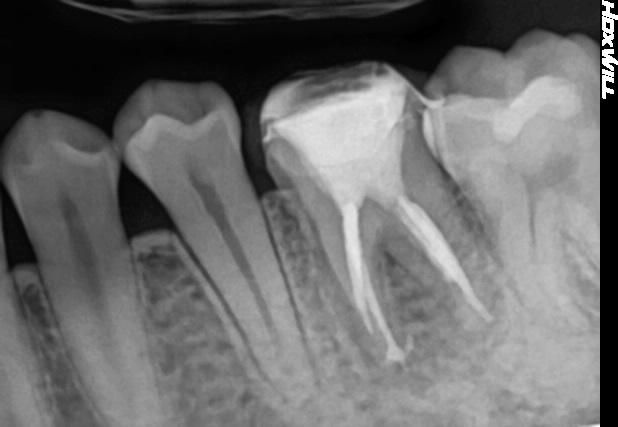

2번째 사진은 치료 전 치근단 사진입니다.

• 2번 째 사진